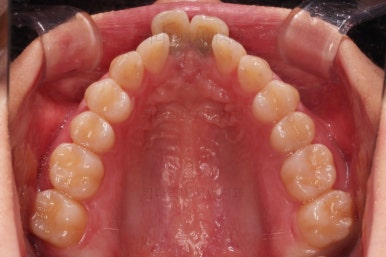

1. 초진

부산개방교합 키다리아저씨치과에 처음 내원 시 입안의 모습입니다.

전반적으로 치열이 삐뚤고요.

앞니쪽이 다물어지지 않는 개방교합(오픈바이트, open bite) 을 보였습니다.

어금니 맞물림을 보면 앵글씨 2급 부정교합 양상이어서 위아랫니가 모두 1대1로 부딪히고 있는 상태였습니다.

개방교합을 닫는 전략은 앞니를 약간 끌어내리고, 어금니를 앞니 위치로 약간 올려서 균형을 맞추는 건데요.

장치 부착은 윗니 어금니부터 했습니다.

미니스크류를 다양하게 활용하여 어금니 높이를 조절합니다.

여전히 앞니는 내버려둔 채로, 윗니는 어금니쪽만 진행하며 아랫니도 장치를 부착했습니다.

난이도가 매우 높은 치료인만큼 미니스크류의 구성과 장치 구성도 매우 복잡했는데요.

윗니 어금니를 뒤로 밀면서 앵글씨 2급 부정교합을 개선해 주고, 높낮이를 조절하면서 개방교합을 개선해 줍니다.